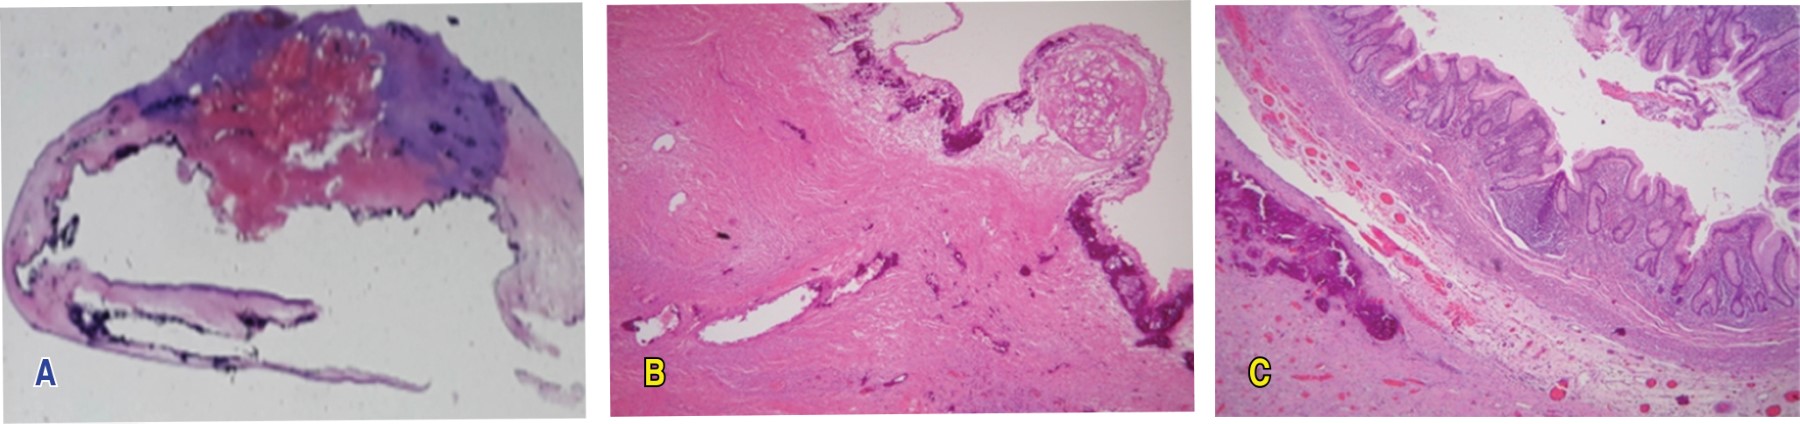

Ese mismo día se procedió a realizar laparotomía exploradora, en la que se encontró un tumor quístico de ovario derecho de 40 × 40 mm, con adherencias a apéndice cecal e intestino delgado. Se realizó apendicetomía incidental por adherencias del tumor más salpingooforectomía derecha (Figuras 3 y 4). No se encontró invasión del tumor hacia las estructuras.

El reporte histopatológico reportó: tumor de ovario derecho compatible con cistadenoma seroso de ovario calcificado, con extensa congestión vascular, edema y necrosis isquémica, apéndice cecal sin alteraciones adherido a la pared del tumor quístico. Se consideró que los cambios isquémicos y las calcificaciones eran compatibles con torsión prenatal del tumor de larga evolución. La salpinge se observó con extensa congestión vascular (Figura 5).

Figura 5